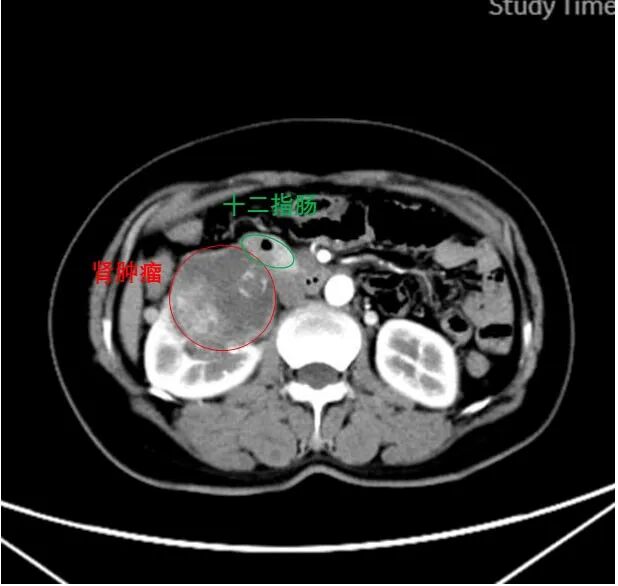

CT影像显示,患者巨大肾肿瘤毗邻十二指肠

经多方咨询,李女士慕名找到青大附院泌尿外科王科教授,王科教授详细查看相关检查,发现肿瘤紧邻下腔静脉、与十二指肠高度粘连,根治性切除难度极大。在反复研究影像学结果、与患者及家属充分沟通后,他决定带领团队接受这个严峻的挑战,为患者实施后腹腔镜右肾根治切除。